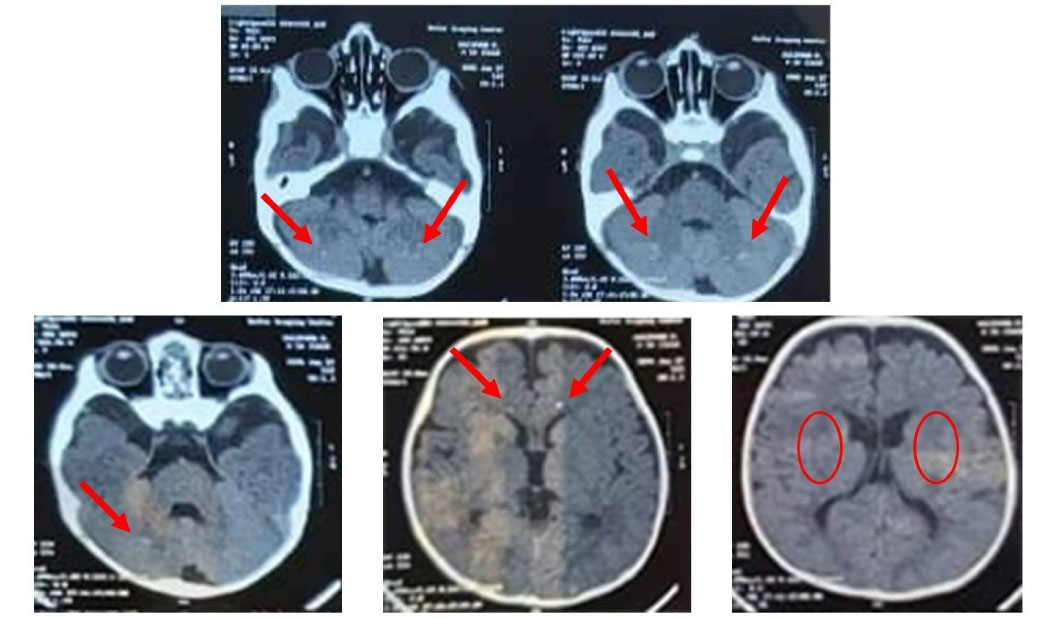

The index patient was a boy, born in 2005 as the first child of healthy consanguineous parents, who referred to Tabriz Genetic Analysis Centre (TGAC) for severe motor dysfunctions, dysphagia, cognitive impairment, and blindness. The patient died at the age of 9 years. The symptoms were initiated with visual problems at one month of age, progressive cognitive decline, gait disturbance, and epileptic seizures above the age of two years. Furthermore, he was admitted several times to the hospital due to shortness of breath and aspiration pneumonia. Magnetic resonance imaging (MRI), and computed tomography (CT) scans were obtained. The brain MRI performed at 2 years of age showed confluent high signal foci at proventricular with matter and subcortical region bilaterally. In addition, mild deep white matter volume loss was evident, and cerebral sulci and ventricles were prominent (Fig. 1). Moreover, the cranial CT scan at 5 years of age revealed a decrease in periventricular white matter with considerable calcification in bilateral basal ganglia, grey-white matter junctions, and cerebellar dentate nucleus. Furthermore, the presence of dilatation of the ventricular system and significant cerebellar hypoplasia with mega cisterna magna were observed (Fig. 2). The family pedigree is depicted in Fig. 3A.

Fig. 1.

CT scan findings showing a decreased density in the periventricular white matter with bilateral calcifications within the basal ganglia, cerebellar dentate nucleus, and grey-white matter junctions.

The family under our study, a patient with the aforementioned symptoms was referred to our center with medical documents compatible with leukodystrophy (Figs. 1 and 2). Therefore, due to the heterogeneity of leukodystrophies, we decided to perform a targeted NGS panel in the index patient, his father, his pregnant mother, and the mother's fetus to diagnose the pathogenicity of the disease. We identified a novel homozygous missense variant (c.2498C>T; p.T833M) in exon 19 of the CSF1R gene in our index patient and fetus. Previously, according to the OMIM database, pathogenic mutations in CSF1R just caused HDSL. The father and mother of the patient both were heterozygous for the mutation, and they were 39 and 34 years old, respectively. Therefore, regarding the fact that HDLS is an autosomal dominant adult-onset disease,

In addition to the age of onset of HDLS in our patient and inheritance pattern in his family, we executed additional clinical investigation to reveal the exact cause of the disease. As well as MRI and CT scan outcomes that were more compatible with BANDDOS rather than HDLS, the patient had pectus abnormalities, respiratory problems, aspiration pneumonia, visual problems, and skeletal abnormalities that all confirmed our hypothesis that our patient had BANDDOS. After identifying the cause of the disease, the mother of the patient chose to abort the fetus, who was homozygous for the mutation, after genetic consulting. Following that, performing ovum donation and preimplantation genetic diagnosis, the pregnant woman achieved a normal pregnancy leading to a child who was wild type for the variant. He is now one-year-old and a healthy child.